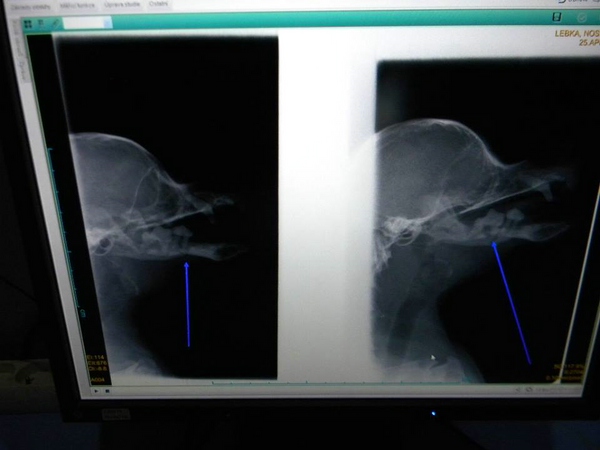

Ivan wurde von der Stadtpolizei aufgegriffen, schnell war klar irgendetwas stimmt nicht, denn sein ganzes Gesicht war geschwollen und er konnte seinen Mund nicht mehr schließen. Bei einer Röntgenuntersuchung wurde festgestellt das sein ganzer Kiefer so schrecklich vereitert war, dass sein Kiefer zweimal gebrochen ist. Er wurde operiert und er hat jetzt Fixateure die den Kiefer zusammenhalten. Er bekommt seit 4 Wochen Antibiotika, das die Entzündung zurückgeht. Bis jetzt sind die Ärzte sehr zufrieden mit der Entwicklung, auf der einen Seite ist der Kiefer schon zusammengewachsen und wenn am 15. Juni die Abschluss Untersuchung positiv ist, werden die Fixateure entfernt und er kann das Tierheim verlassen.